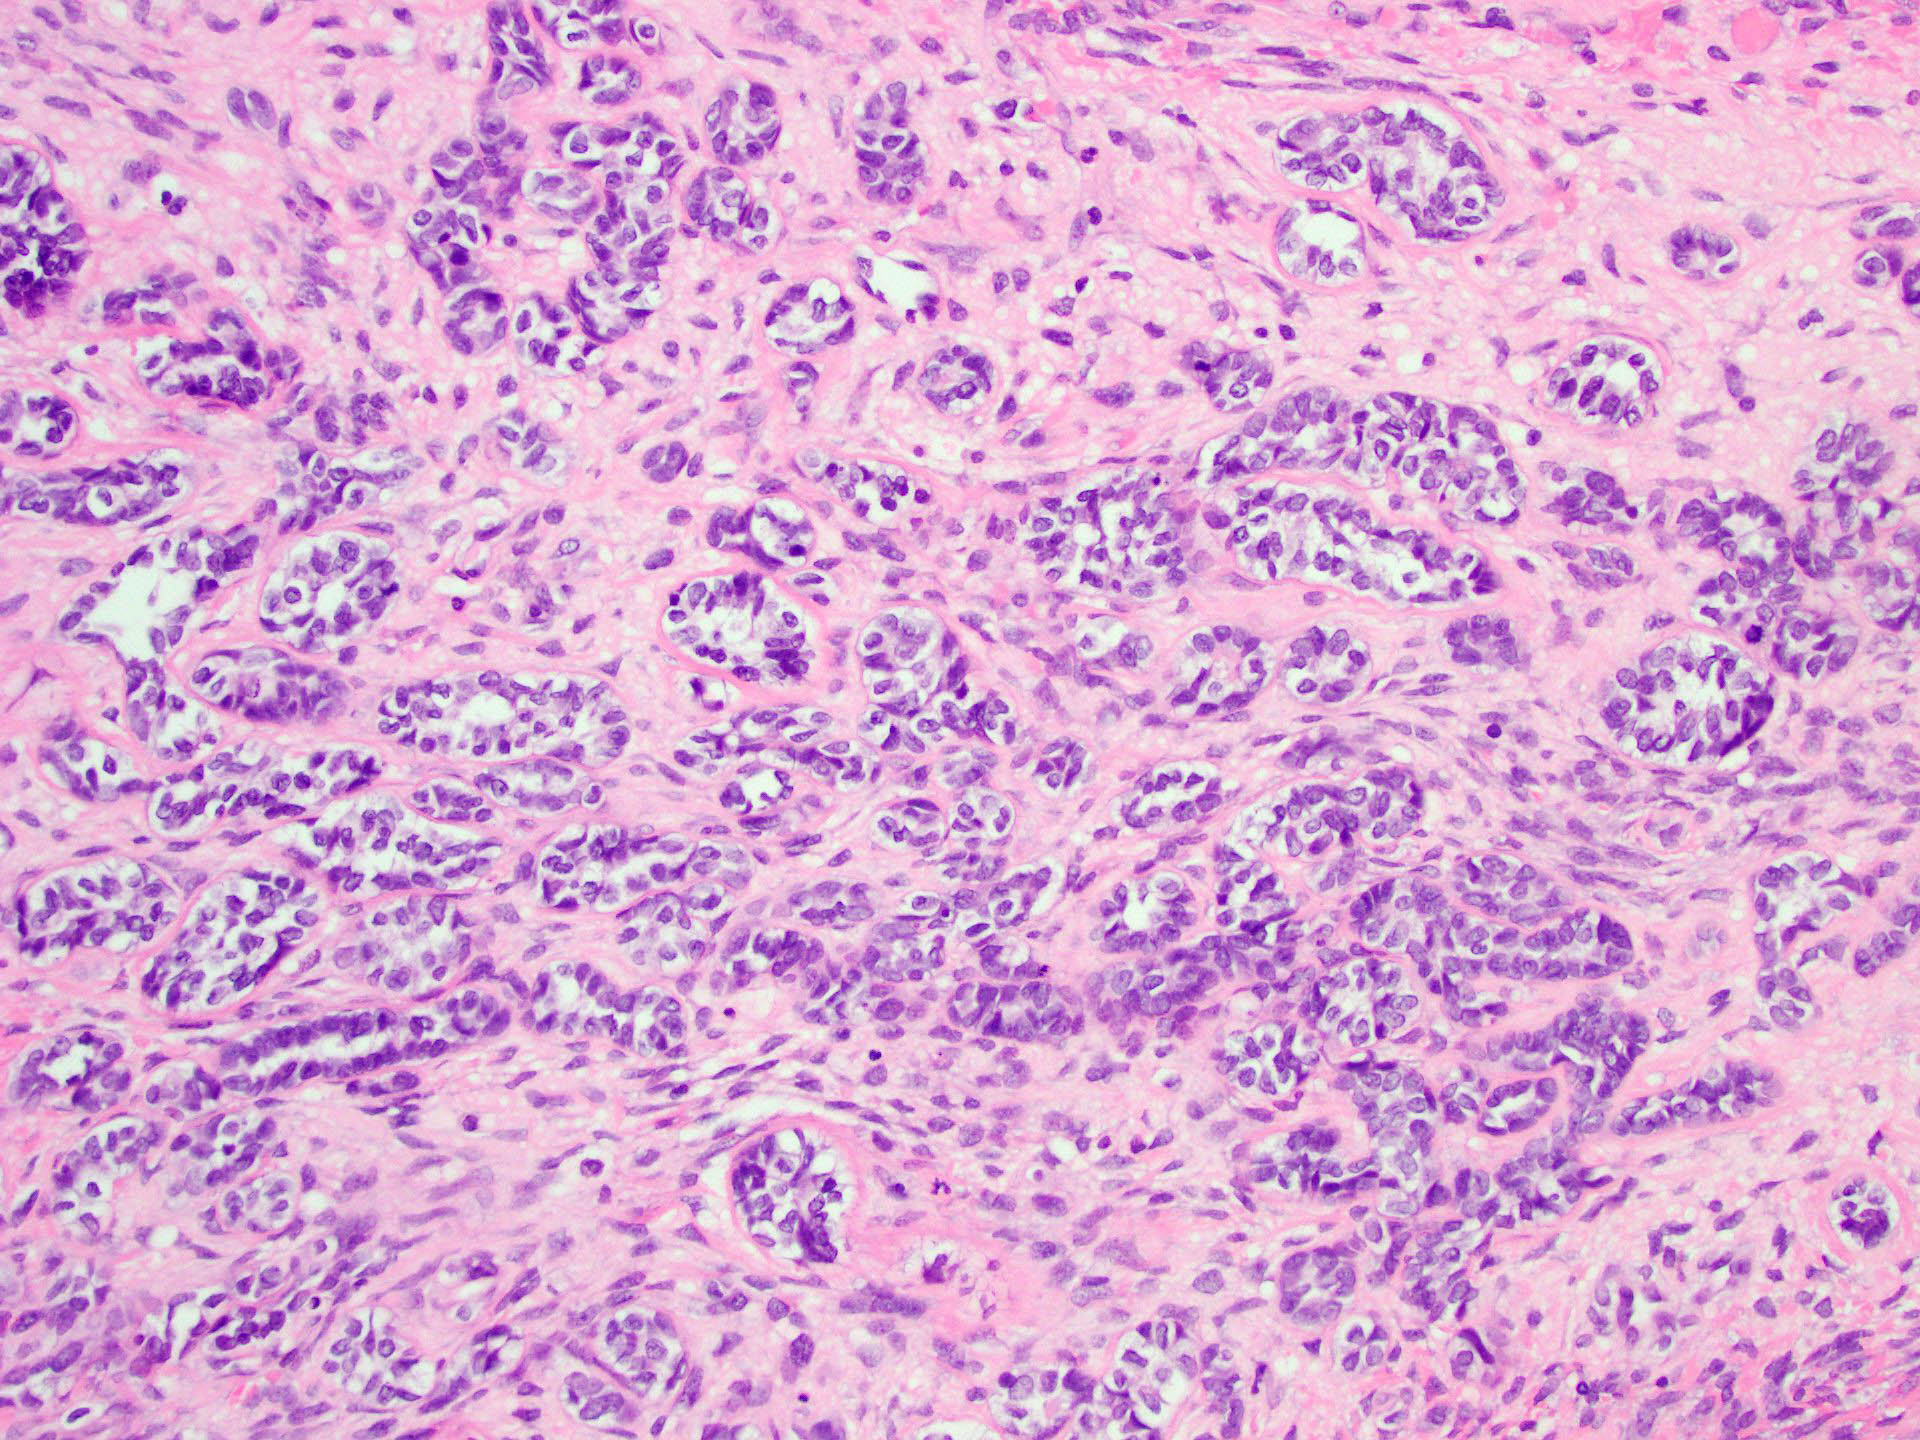

Microscopic (histologic) description

- Tubular pattern (most common and usually present at least focally) with solid or hollow tubules

- Cuboidal or columnar cells

- Bland oval to round, monotonous nuclei

- Pale cytoplasm

- Lipid rich or oxyphilic variants may be associated with Peutz-Jeghers syndrome

- Other patterns: trabecular, diffuse, alveolar, pseudopapillary, reniform, pseudoendometrioid, spindled

- Absent to very rare Leydig cells

- Pathologic features predictive of malignant behavior include 5 mitoses per 10 high power fields, severe cytologic atypia, necrosis and size > 5 cm

- Reference: Am J Surg Pathol 2005;29:143

Microscopic (histologic) images

A 40 year old woman is seen in the clinic with complaints of irregular uterine bleeding and pelvic fullness. Transvaginal ultrasound shows a 9 cm right ovarian mass. The mass is surgically removed and a pathologic examination shows the features in the picture above. The mass is positive for inhibin and SF1. The tumor is negative for EMA, PAX8, MelanA and chromogranin. In which of the following general categories does this tumor belong?

C. Pure sex cord tumor. Sertoli cell tumor is a pure sex cord neoplasm of the ovary composed of Sertoli cells most commonly arranged in a tubular pattern. Sertoli cells are positive for inhibin and SF1. Answer D is incorrect because no Leydig cells, which are positive for MelanA and are stromal in nature, are present. Answer B is incorrect because the tumor is negative for neuroendocrine markers. Answer A is incorrect because the tumor is negative for EMA and PAX8.